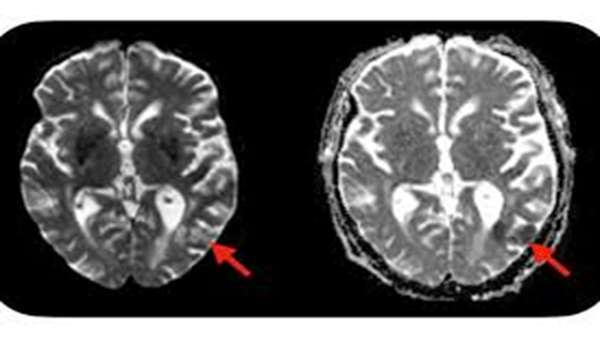

این عوارض در افراد مختلف بسیار متفاوت است و میتواند شامل هر عارضهای از اختلال تمرکز، مشکلات حافظه، گیجی، مشکل در خواندن و سردرد گرفته تا تشنج، سکته مغزی و تورم مغزی باشد. پزشکان این عوارض را عمدتاً با استروئیدهای با دوز بالا و گاهی اوقات با درمانهای تعدیل کننده سیستم ایمنی که سعی در کاهش التهاب دارند، مدیریت میکنند. این بسیار مفید است که بدانیم چه کسانی در معرض خطرناکترین عوارض جانبی هستند، زیرا متأسفانه درمانهای استروئیدی و ضدالتهابی میتوانند اثر ضد سرطانی سلولهای CAR-T را کاهش دهند و پزشکان ترجیح میدهند تا حد امکان از استفاده از آنها خودداری کنند.